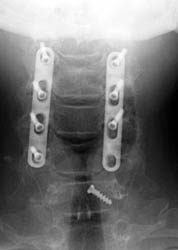

AP and lateral radiographs taken 5 days later, while still in the

hospital. Note migration of left C6 screw. It has loosened and fallen out. This

screw was not causing symptoms and decision was made to conservatively manage

the patient and keep in rigid cervical collar until the bone graft matured in

2-3 months.